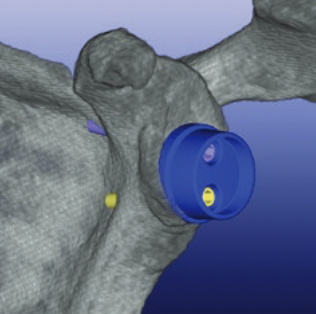

Patient specific instrumentation

Zimmer PSI Trabecular metal rTSA

Zimmer Signature One Surgical technique PDF

Metaglene / baseplate fixation

Screws as long as possible

- inferior screw - long into scapular pillar

- superior screw - aim for coracoid

- anterior / posterior screws - convergent / divergent